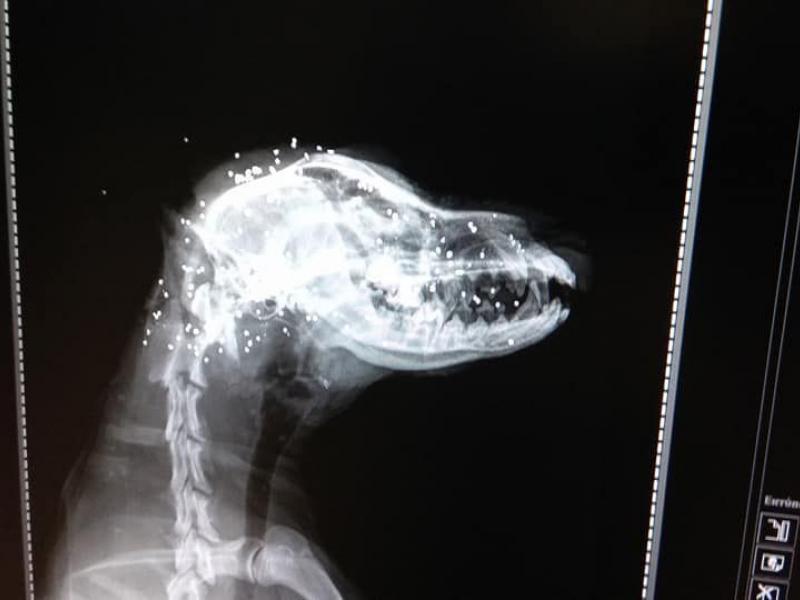

08.05.2018 - 13:07 Οργή για ασυνείδητο που πυροβόλησε εξ΄επαφής σκύλο [πολύ σκληρές εικόνες] Το ανθρωπόμορφο τέρας που πυροβόλησε χθες εξ επαφής με κυνηγετικό όπλο ένα μικρό σκυλάκι στην Ηλεία αναζητούν η ΕΛ.ΑΣ και οι δικαστικές Αρχές ΚΟΙΝΩΝΙΑ Οργή για ασυνείδητο που πυροβόλησε εξ΄επαφής σκύλο [πολύ σκληρές εικόνες]